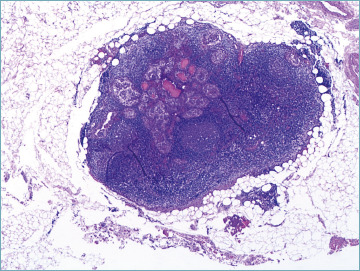

目的:美国甲状腺协会(ATA)更新了甲状腺癌治疗指南,根据临床病理特征采用了一种不那么激进的方法。因此,与全甲状腺切除术相比,行肺叶切除术的可能性显著增加。大多数甲状腺癌是惰性的,预后良好,而只有15%的高分化癌(包括乳头状甲状腺癌(PTC))患者在诊断时为局部晚期甲状腺癌(LATC)。我们回顾了过去十年来治疗甲状腺癌的实践。方法:对2010年1月至2020年12月1057例甲状腺单发良、恶性病变患者进行回顾性分析。结果:77%为女性,中位年龄49.3岁。307例恶性诊断(29.05%),其中经典PTC 196例(61.6%),侵袭性PTC 38例(12%),多为高细胞变异(30例,9.4%)。在恶性病例中,显微镜下发现84例(26.4%)为多灶性病变。采用ATA风险分布,低危239例,中危68例。第二次手术共对150例患者进行了评估,显示42例患者在另一侧肺叶有额外的甲状腺癌灶(26例单发灶vs 16例多发灶)。甲状腺周围淋巴结转移10例。结论:我们的数据可以作为进行纵向研究的基础,以确定哪些危险因素可以预测双侧受累,并建议量身定制的手术方法。

Results: Among these cases, 77% were women with a median age of 49.3 years. The series involved 307 malignant diagnoses (29.05%) including 196 (61.6%) classic PTC and 38 (12%) aggressive variants of PTC, mostly tall cell variant (30 cases, 9.4%). Among malignant cases, multifocality was microscopically documented in 84 cases (26.4%). Using the ATA distribution of risk, there were 239 cases in the low risk and 68 in the intermediate risk categories. Second surgery was assessed in a total of 150 cases, showing 42 cases with additional thyroid cancer foci in the other lobe (26 single vs 16 multiple foci). Ten cases had metastatic perithyroidal lymph nodes.